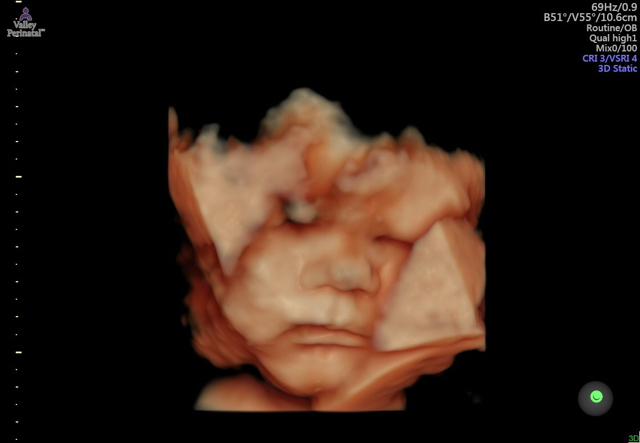

34 weeks!

5 more weeks until my scheduled c section! Little man has a full head of hair! Can’t wait to meet him 💙